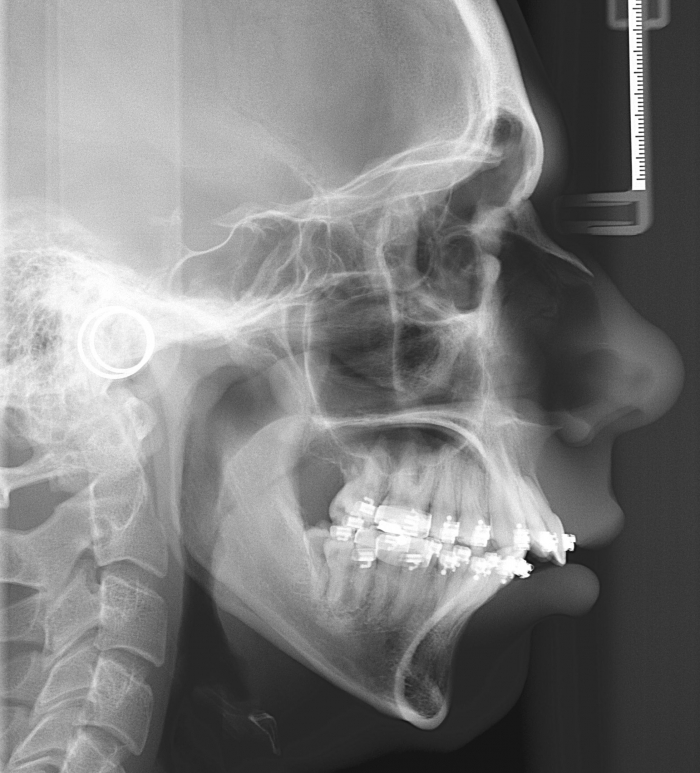

Telerradiografia perfil inicial - Clínica Cliniface

Telerradiografia perfil inicial